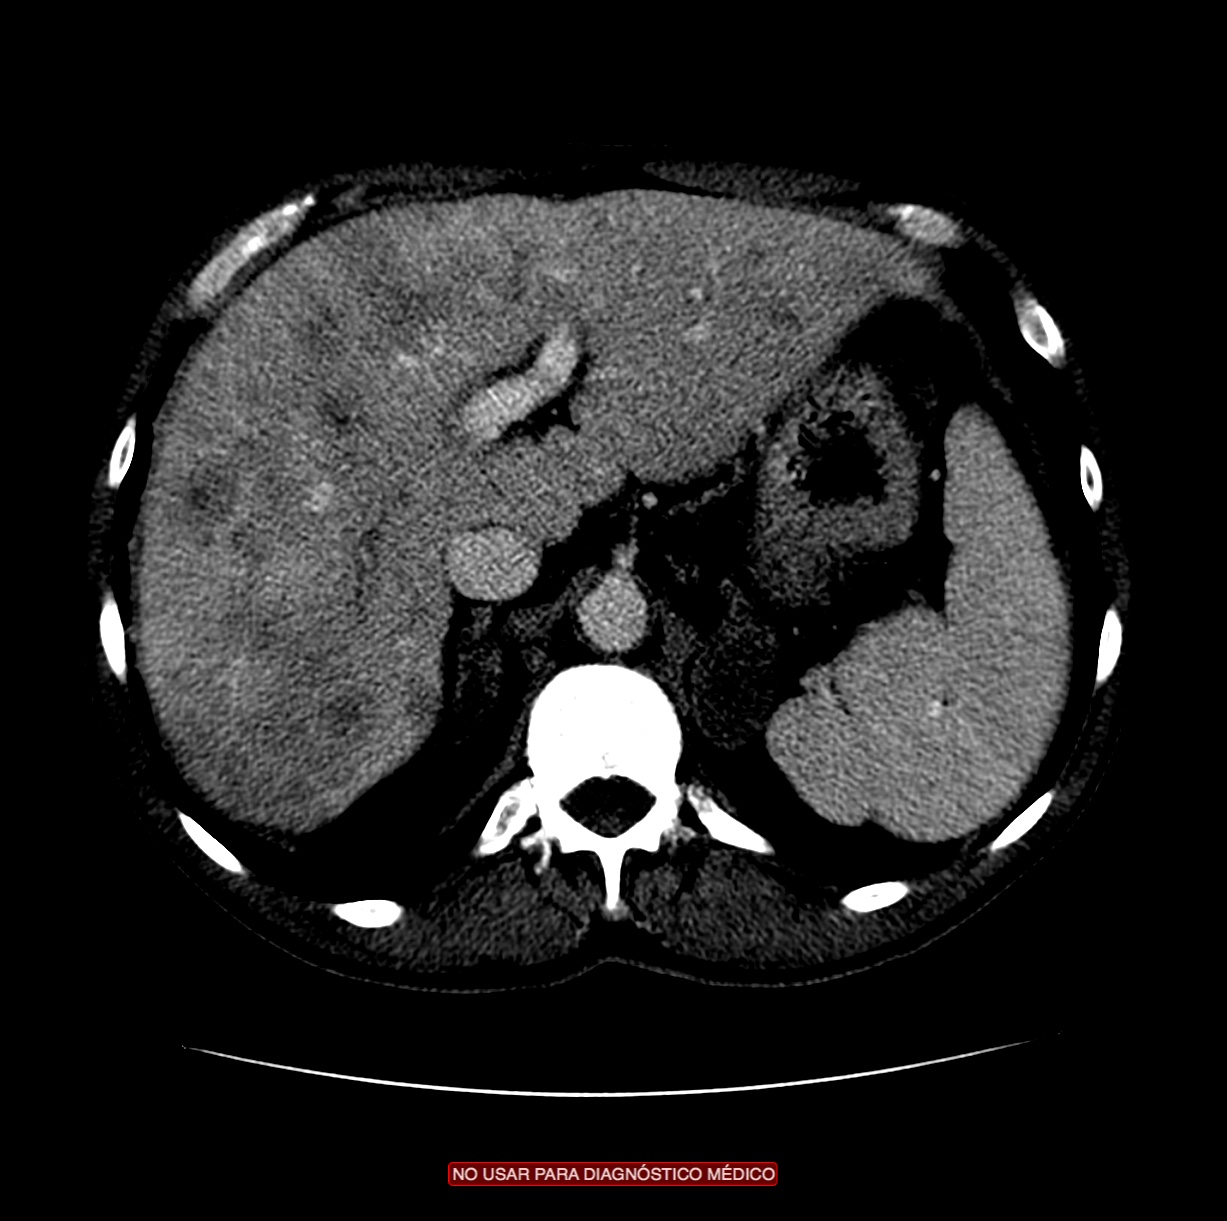

CASO CLÍNICO: Recopilatoción.

Paciente de 59 años con antecedentes personales de Cá de vejiga.

Se le realiza una Uro-Tc por seguimiento al año, aunque en esta ocasión el paciente refiere episodio de hematuria.

Tras el tratamiento de la recidiva y nefrostomía para la hidroureteronefrosis, vuelve acudir al hospital a los 9 meses por episodio de dolor en FD y malestar general. Se realiza una ecografía de urgencias.

Se realiza nueva TC bifásico abdominopélvio y Uro TC.

- Paciente con numerosas recidivas por Cá vejiga.

- Ha desarrollado un tumor metacrónico en pelvis renal derecha, también responsable de la hidroureteronefrosis.

- Mala evolución radiológica del proceso a expensas de metástasis pulmonares y hepáticas.